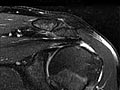

Magnetic Resonance Imaging (MRI) of the Shoulder

Magnetic resonance imaging (MRI) is a test done with a large machine that uses a magnetic field and pulses of radio wave energy to make pictures of the shoulder. Muscles, ligaments, cartilage, and other joint structures are best seen with an MRI. In many cases an MRI gives information about structures in the body that can't be seen as well with an X-ray, ultrasound, or CT scan.

For an MRI test, you are placed inside the magnet so that your shoulder is inside the strong magnetic field. An MRI can find changes in the structure of organs or other tissues. It also can find tissue damage or disease, such as infection or a tumor. Pictures from an MRI scan are digital images that can be saved and stored on a computer for further study. The images also can be reviewed remotely, such as in a clinic or an operating room. Photographs or films of selected pictures can also be made.